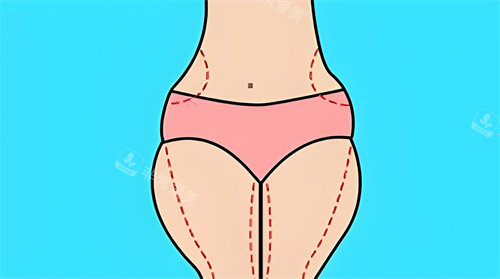

主治医生金院长在面诊时,用3D扫描技术生成了我腿部的三维模型,在屏幕上模拟出不同吸脂量对应的腿型变化,比较终确定右侧大腿抽取300ml、左侧280ml脂肪,小腿部分采用光纤溶脂技术。

金院长在设计方案时强调"保留1.5cm脂肪层"的原则,避免出现皮肤凹陷。

针对我膝盖内侧的脂肪堆积,他计划采用微小切口技术;而小腿部分则结合肌肉放松术,改善我长期穿高跟鞋导致的肌肉紧张。